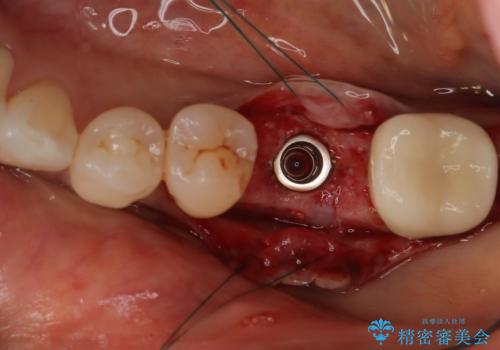

インプラント治療を希望されたため、インプラントを埋入し咬合機能を回復していきます。

骨の量は十分あったため、比較的短期間で治療は終了しました。

安定した咬み合わせとなり、痛みもなく安心して噛めるようになりました。